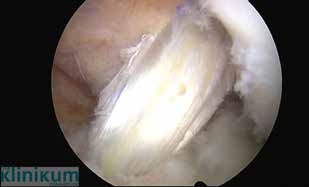

Bei zusätzlichen traumatischen Meniskusrupturen, die rekonstruierbar sind, sollten diese bei Sportlern refixiert werden. Die Refixation sollte mit der Rekonstruktion des vorderen Kreuzbandes verbunden werden. Die konservative Therapie der vorderen Kreuzbandverletzung erfolgt mit einem muskulären Kräftigungsprogramm und sensomotorischem Training. Das sportliche Aktivitätsniveau wird angepasst. Der Erfolg der Therapie muss regelmäßig überprüft werden. Bei „Givingway-Phänomen“ und hoher Aktivität wird zur Verhinderung von Meniskus- und Knorpelschäden bei chronischen Instabilitäten zur operativen Versorgung geraten. Wissenschaftliche Arbeiten haben gezeigt, dass nicht das Lebensalter, sondern die Aktivität Sekundärschäden bei Kreuzbandinstabilität begünstigt 4. Die Indikation zur operativen Versorgung besteht auch beim älteren Sportler, wenn er durch Giving-way-Phänomene im Sport oder im täglichen Leben beeinträchtigt ist. Eine bereits fortgeschrittene Kniearthrose stellt dagegen eine Kontraindikation für einen Bandersatz dar. Die vordere Kreuzbandrekonstruktion wird heute in arthroskopischer Versorgungstechnik durchgeführt. Frische Verletzungen können mit einer primären Ersatzplastik, einer transossären Re-Insertion bei gleichzeitiger Augmentation (bei femoralem Abriss) oder mit einer knöchernen Refixation bei knöchernem Eminentiaausriss versorgt werden. Im deutschsprachigen Raum werden als häufigste Transplantate die Semitendinosus-/Gracilissehne, das mittlere Drittel der Patellarsehne oder ein Quadrizepssehnenanteil verwendet (Abb. 2). Die Transplantatwahl richtet sich nach den individuellen Bedürfnissen des Sportlers, der Sportart, dem Beruf und den körperlichen Gegebenheiten. Ziel ist eine möglichst anatomiegerechte Rekonstruktion des vorderen Kreuzbandes 5.

Für den Erfolg der Kreuzbandersatzplastik ist eine korrekte Tunnelplatzierung entscheidend. Auf eine impingementfreie Implantation des Bandes ist zu achten. Die Platzierung des femoralen Bohrkanals erfolgt über das anteromediale Zugangsportal bei Flexion des Kniegelenkes über 110°. Die Transplantatfixation erfolgt gelenknah mit bioresorbierbaren Interferenzschrauben oder gelenkfern mit Buttons (Abb. 3). Durch die Beschreibung des Aufbaus des vorderen Kreuzbandes mit seiner flachen/rechteckigen femoralen und flachen c‑förmigen tibialen Insertion durch Smigielski 6 entwickeln sich mit Hilfe spezieller Zielgeräte neue Operationstechniken.